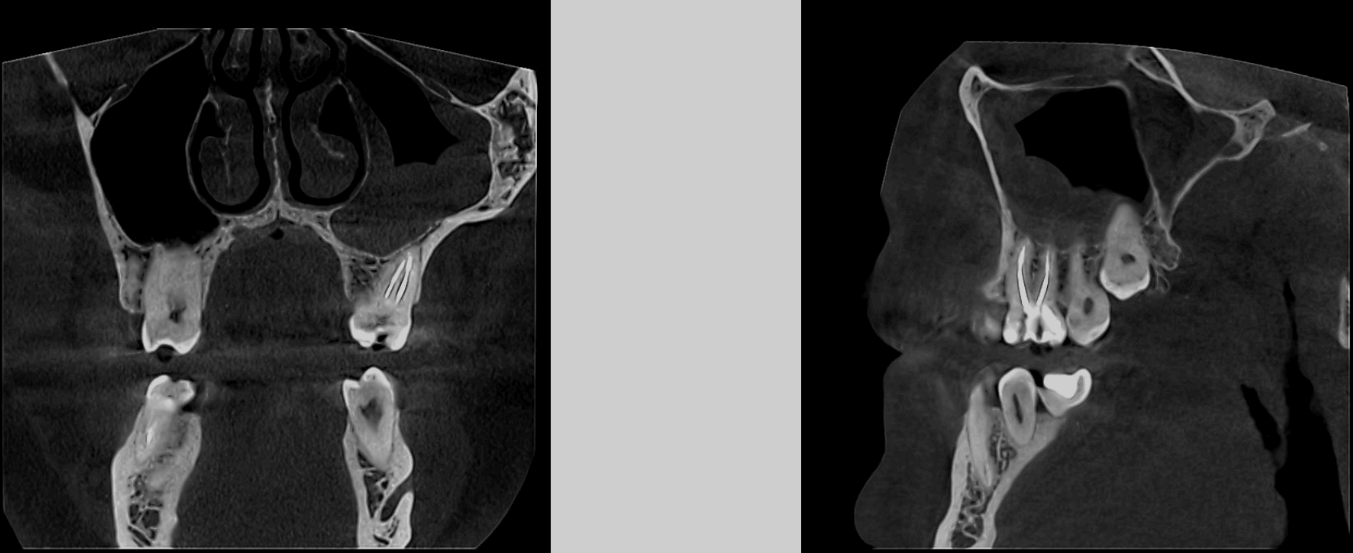

| Лечение зубов под микроскопом дает врачу огромное увеличение от 10х до 25х, а также качественный свет до 100 тыс. люкс (прямые солнечные лучи в тропиках). Это позволяет врачу раньше найти проблему и убрать только плохие инфицированные ткани зуба, максимально сохраняя здоровые. Так, в следующем клиническом случае мы под микроскопом (10х увеличение!) нашли скрытый кариес между зубами 2.4/2.5 (рис. 2). |

![]() Рис. 2. До лечения 2.4/2.5 |